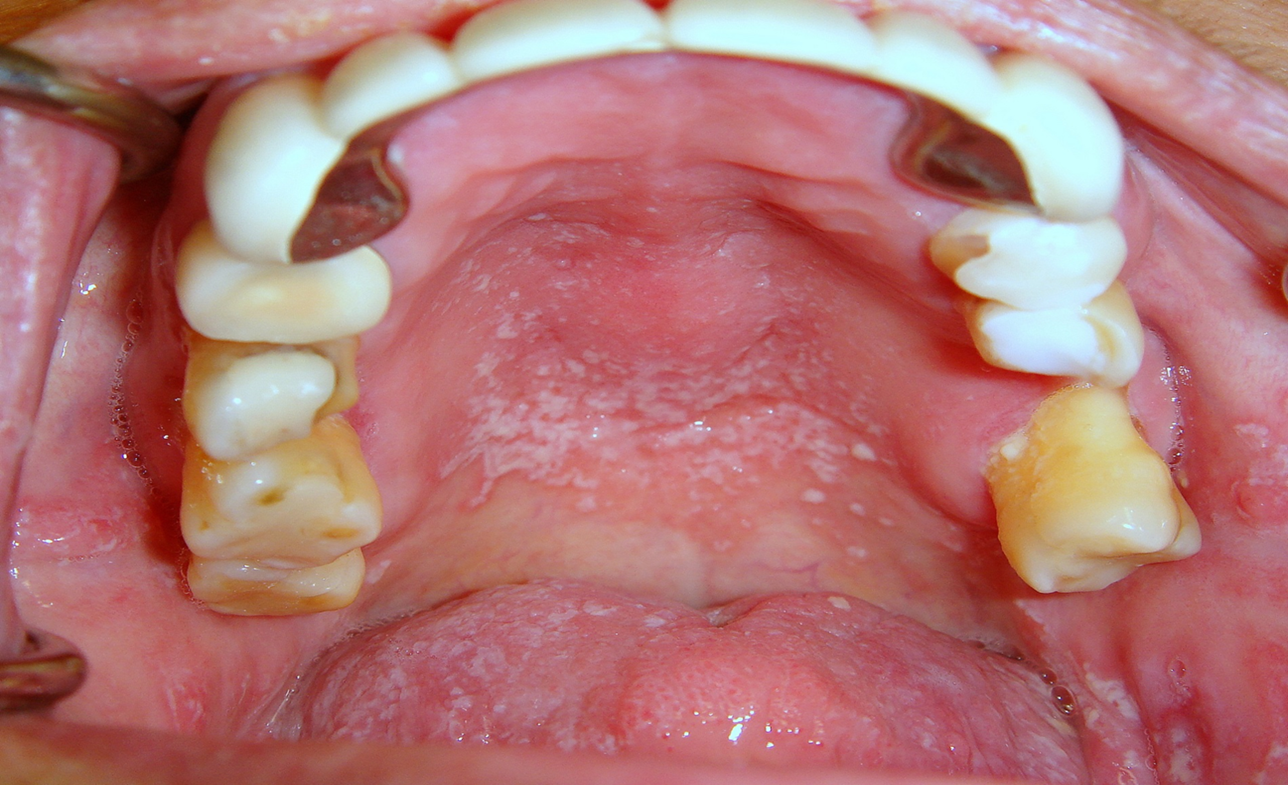

Diagnosis of xerostomia and salivary gland hypofunction is dependent upon a careful and detailed history and thorough oral examination. The term is derived from the greek words xhros xeros meaning dry and stoma stoma meaning moutha drug or substance that increases the rate of salivary flow is termed a sialogogue. It occurs when salivary glands in your mouth dont produce enough saliva. Xerostomia is the subjective sensation of dry mouth which is often but not always associated with hypofunction of the salivary glands.

Xerostomia can make it difficult to speak eat and digest food and can lead to malnutrition. Xerostomia the subjective complaint of dry mouth and hyposalivation remain a significant burden for many individuals. Review the latest covid 19 resources and research advancements. It may or may not be associated with decreased salivary gland function.